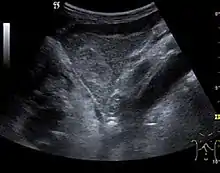

Liver cysts

They can be single or multiple, with variable size, generally less than 20 mm (congenital). Rarely, sizes can reach several centimeters, leading up to the substitution of a whole liver lobe (acquired, parasitic). They may be associated with renal cysts; in this case the disease has a hereditary, autosomal dominant transmission (von Hippel Lindau disease).

The ultrasound appearance is a well defined lesion, with very thin, almost unapparent walls, without circulatory signal at Doppler or CEUS investigation. The content is transonic suggesting fluid composition. The presence of membranes, abundant sediment or cysts inside is suggestive for parasitic, hydatid nature. Posterior from the lesion the acoustic enhancement phenomenon is seen, which strengthens the suspicion of fluid mass. They typically displace normal liver vessels but no vascular or biliary invasion occurs.

- Liver cyst